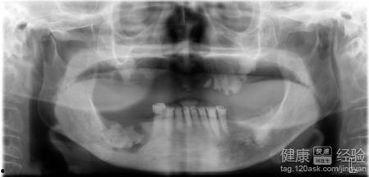

首先,我们要了解什么是牙胚。牙胚是牙齿发育的最初形态,它存在于我们的牙槽骨中。在婴儿时期,我们的牙齿就是从牙胚发育而来的。但是,随着年龄的增长,我们似乎已经告别了长牙的日子。那么,成人怎么长出牙胚呢?

视频中,我们看到了牙胚从牙槽骨中逐渐发育,最终形成完整的牙齿。这个过程虽然复杂,但在视频的讲解下,却显得如此简单易懂。